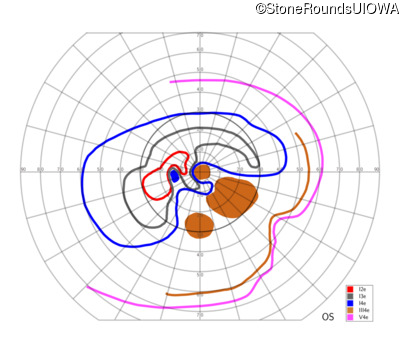

AR Stargardt Disease (IIA)

AR Stargardt Disease (IIA)

| Age at visit: 12 years |

| Age at visit: 13 years |

| Age at visit: 15 years |

| AR Stargardt Disease | ABCA4 | Leu541Pro CTA>CCA, Ala1038Val GCC>GTC | Gln1003Stop CAG>TAG | AR |